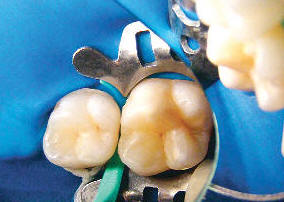

Radiolucidez limitada al 1/3 externo de la dentina

Después de aislar el diente con un dique de goma y la colocación de cuñas para separar los dientes, la superficie del diente se prepara con un 15% de gel de HCL para abrir el sistema de poros del cuerpo de la lesión . A continuación, la superficie se enjuaga y  se seca con etanol, luego se continua secando con aire a presión. La resina Infiltrante Icon, que tiene un coeficiente de penetración alto, se aplica sobre la lesión, el exceso de material se retira, y el material es curado por luz. El fabricante recomienda la aplicación de una segunda capa del infiltrante, seguido de curado por luz adicional.

Aislación y separación de dientes

Gel de HCL

Se enjuaga y se seca con etanol

Resina infiltrante

Fotocurado